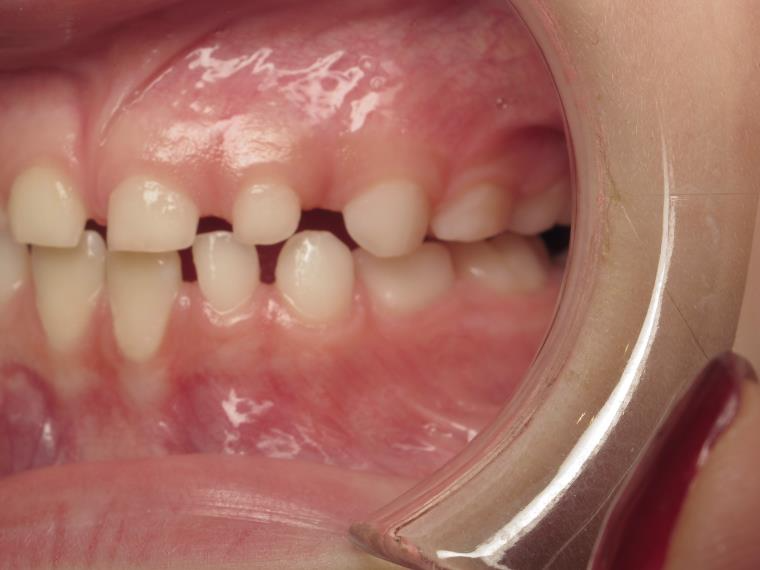

12 béance inversé droit 4 ans

inversion postérieur coté droit et espace entre les dents du haut et du bas (diastèmes)